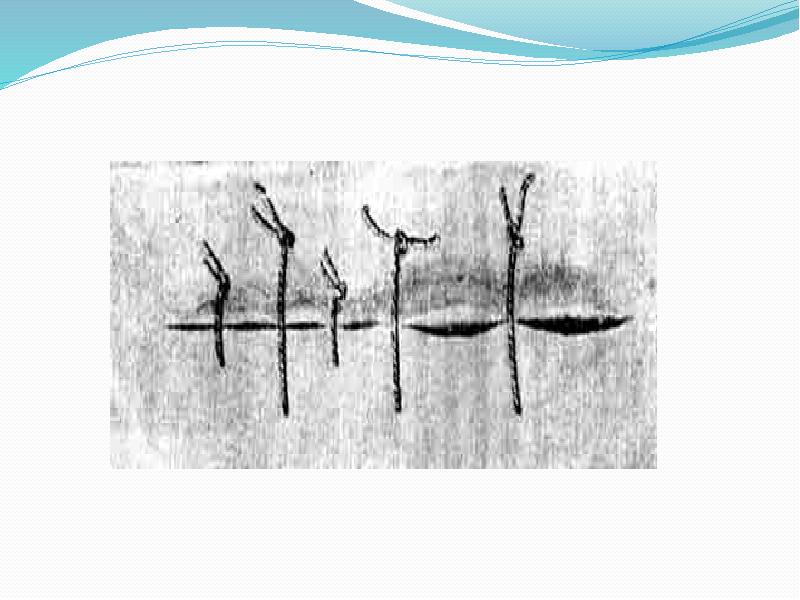

- 26. Компрессионно-декомпрессионный шов по Д.Л. Пиковскому состоит из простых узловых швов, отличающихся